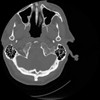

4 CEREBRO,,Vol,0.5,CEREBRO,,